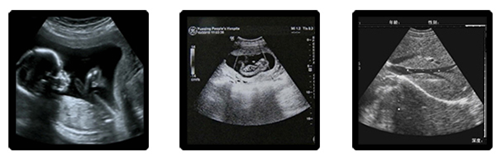

越来越多的妈妈选择四维彩超来做孕期检查,和普通彩超相比,四维彩超直观,立体,全方位成像,能够更好地观察胎儿的生长发育情况,但是也有不少妈妈并不清楚做四维彩超的一些注意事项,做四维彩超要空腹吗?

安琪儿妇产医院斥巨资引进美国Voluson E8 TruScan四维彩超,其出色的人体工程学设计,每秒钟可实时获得46幅容积图像,能直观、立体的观察和显示人体器官的动态和三维结构,通过四维(全方位)立体成像,清晰并动态记录宝宝在子宫内的活动和成长历程。该技术获得美国FDA认证,不存在射线,光波和电磁波等方面的辐射,为您和宝宝提供健康保障,使您轻松愉悦的享受和宝宝的第一次“约会”。